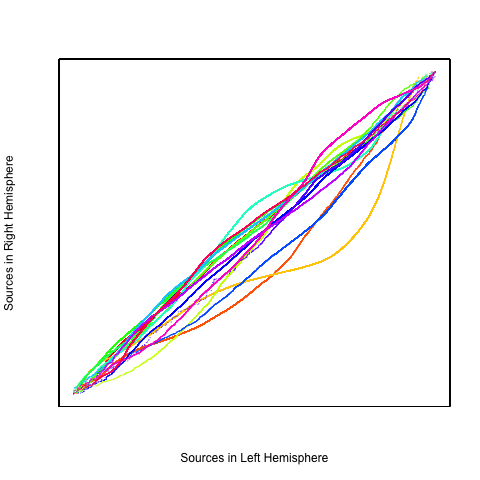

This particular analysis focused on 20 subjects picked from the ADHD-200 data set. Data were processed via the NITRC 1,000 Functional Connectome processing scripts (Mennes et al., 2012). In summary, images were slice-time corrected, deobliqued, skull stripped, smoothed and registered to a 3 mm3 MNI template. The data were then registered to ICBM 2009a nonlinear symmetric templates generated by the McConnell Brain Imaging Centre (Fonov et al., 2009b, 2011a). Each fMRI scan contains voxels measured at time points. Figure 10 and Figure 11 are the QQ plot and scatter plots of the estimated sources extracted by ordinary gICA in the left and right hemispheres. Most of the estimated sources are close to the line, which suggests that the marginal distributions of left and right hemispheres are similar. H-gICA can benefit from this apparent homotopy.

Our procedure is as follows. Each fMRI scan was separated into left and right hemispheres. Thus, each hemisphere contained voxels. Similar to standard group ICA (Calhoun et al., 2001b), a dimension reduction using PCA was applied to each hemisphere of each subject. 15 PCs are obtained for each hemisphere. A group data matrix was generated by concatenating the reduced data of both hemispheres of the 20 subjects in the temporal domain. Thus, the aggregated matrix has dimension , where , , and . Our algorithm of homotopic group ICA is then applied on this matrix. Fifteen estimated independent components are postulated by H-gICA. As shown in Figure 12, out of the 15 components, several brain networks were found including: the visual network 12, the default mode network 12, the auditory network 12, and the motor network 12. Compared with the ICs obtained from ordinary gICA, shown in 12, 12, 12 and 12, H-gICA improves the estimation of all of these sources by yielding substantially more clearly delineated networks.